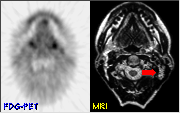

Shown above is a pre-treatment MRI image of a 58 year-old female with a palpable mass in the base of the tongue. The MRI was reported as negative.

Shown above are pre-treatment FDG-PET images from this patient. Increased metabolic activity is notable on the right side of the tongue (red arrow). Biopsy of the mass revealed squamous cell carcinoma.

FDG-PET images taken 10 weeks following completion of radiotherapy showed symmetrical FDG uptake with no abnormality in the affected area. The patient has remained clinically free of disease and the mass is not palpable on physical exam. This case demonstrates the sensitivity of FDG-PET in the detection of small, metabolically active tumors and the usefulness of PET in determining resolution of tumor following treatment.